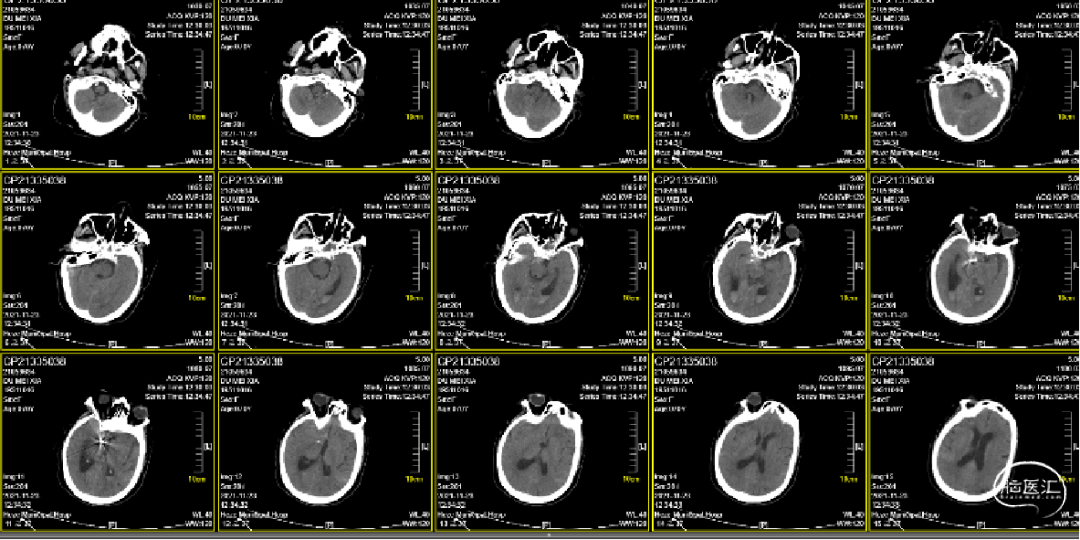

术前影像

术前颅脑CT提示蛛网膜下腔出血。

术后第一天复查颅脑CT:蛛网膜下腔出血减少,未见明显新发脑梗死等改变。